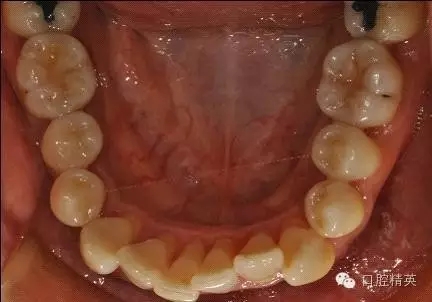

治療后:炎癥得到控制,牙周袋已消除,松動度有所改善。

牙周固定后: